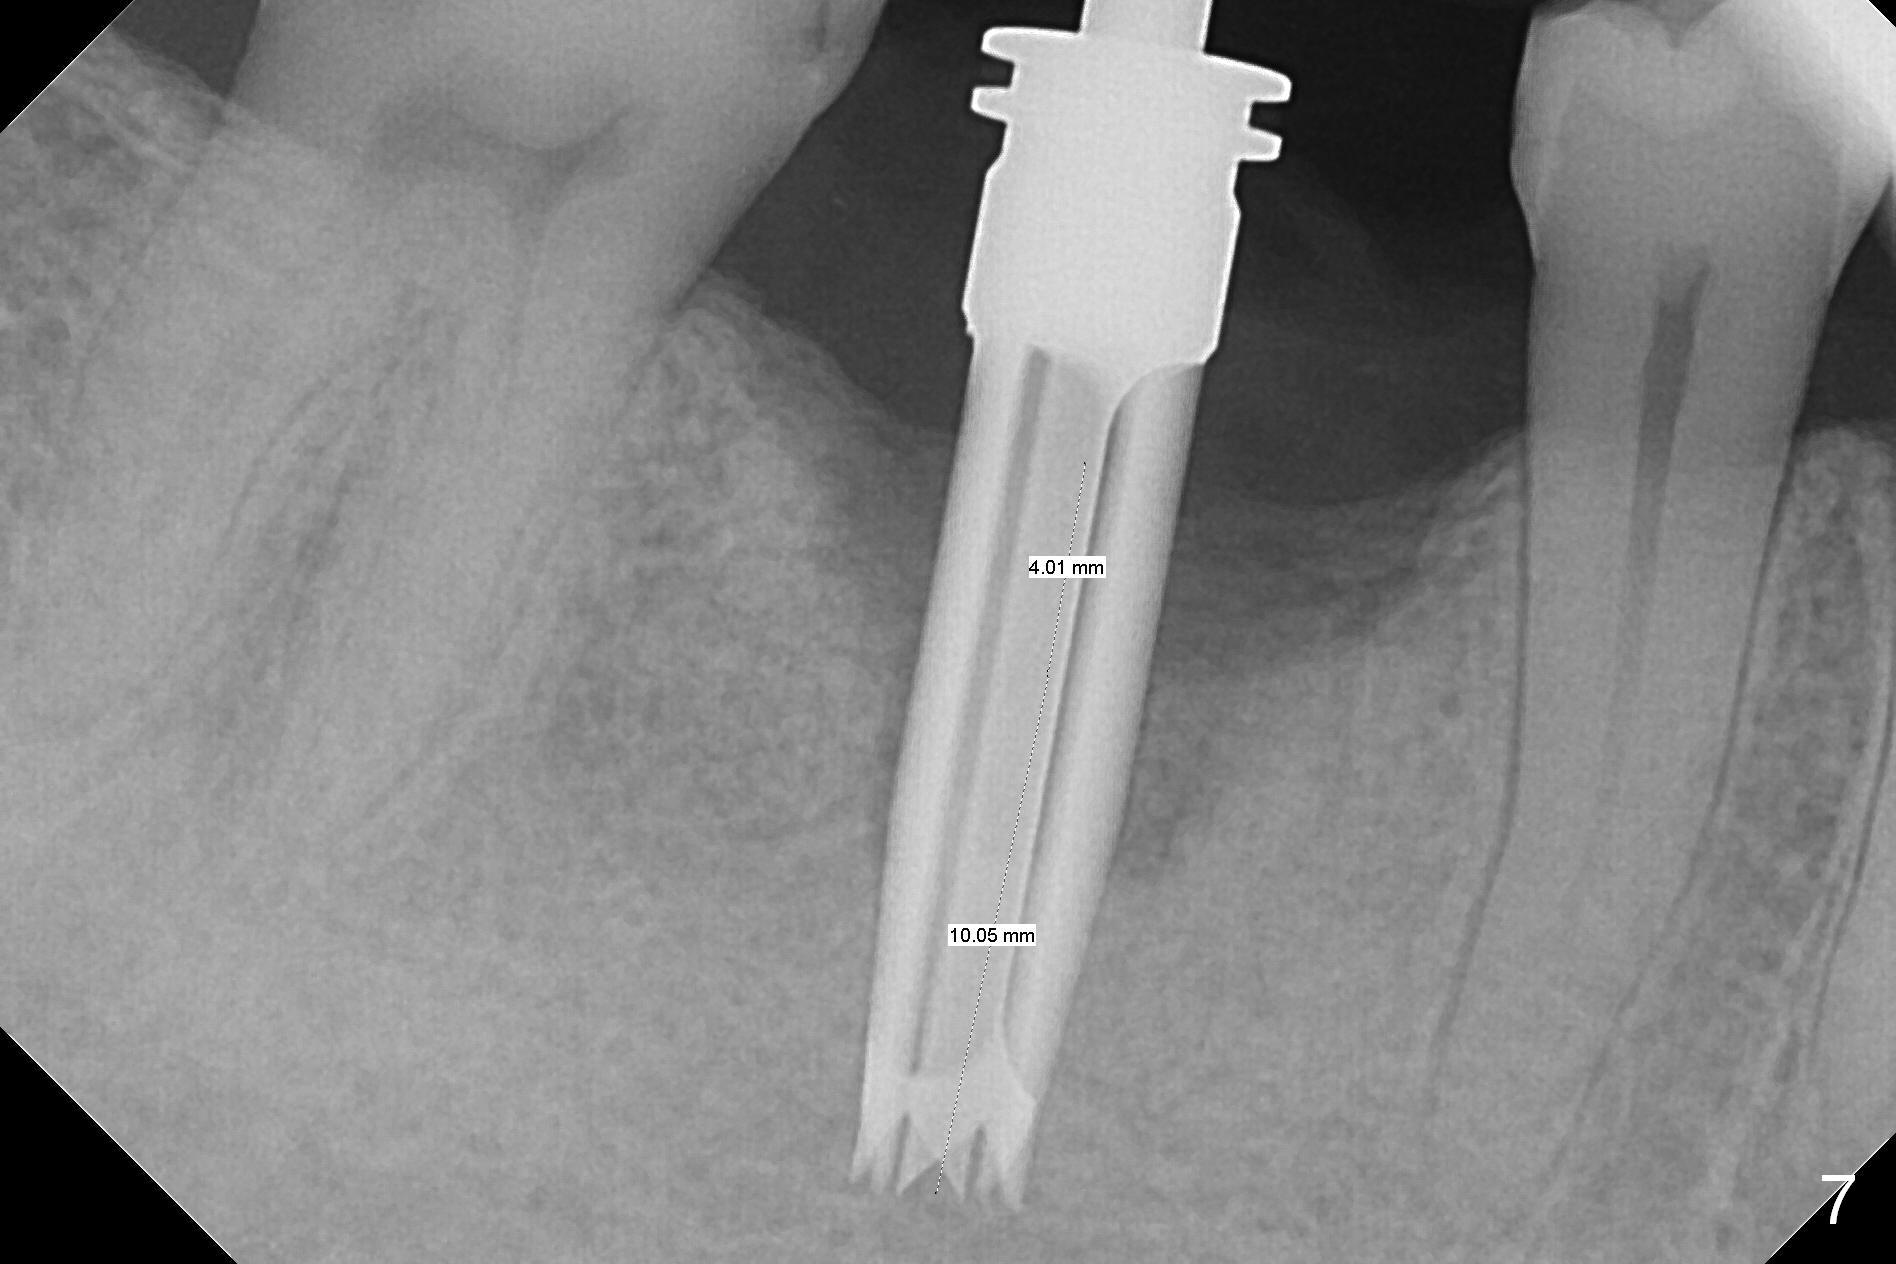

A 49-year-old man develops acute abscess of the lower right quadrant (Fig.3-5) secondary to periimplantitis at #30 (Fig.1,2,6). The latter is probably due to buccal placement (Fig.6 (*: buccal plate)). After removal of the infected implant, an osteotomy is established as lingual as possible using single drill modality (Fig.7 (4.3 mm Magic Drill after 1.6 mm pilot drill and Marking Bur, then Final Drill). With the single drill, the osteotomy does not shift buccally in spite of the lower buccal plate. A 5x9 mm IBS implant is placed lingually as planned (Fig.8 (>40 Ncm)), followed by an angled abutment (5 mm x 15° (4 mm)) (Fig.9 A). The buccal gap is filled with autogenous bone, allograft (.5-1.5 mm) and Osteogen (Fig.10 *), covered by resorbable and non-resorbable membranes. After suturing, periodontal dressing is applied.